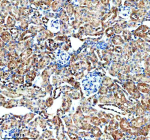

IHC analysis of GHRHR using anti-GHRHR antibody. GHRHR was detected in a paraffin-embedded section of human prostate cancer tissue. Heat mediated antigen retrieval was performed in EDTA buffer (pH 8.0, epitope retrieval solution). The tissue section was blocked with 10% goat serum. The tissue section was then incubated with 2 ug/ml rabbit anti-GHRHR antibody overnight at 4oC. Peroxidase Conjugated Goat Anti-rabbit IgG was used as secondary antibody and incubated for 30 minutes at 37oC. The tissue section was developed using an HRP secondary and DAB substrate.